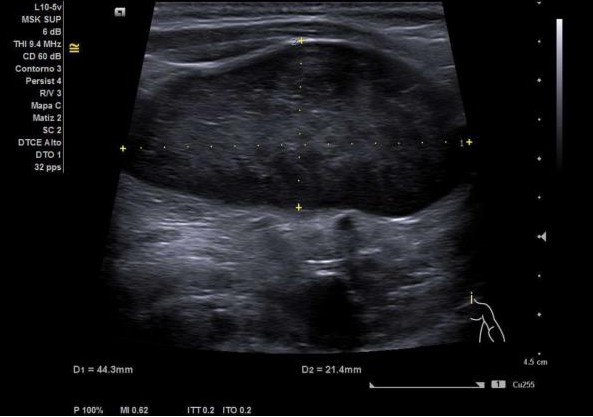

Dada la clínica y la exploración física, se decide realizar ecografía clínica en el Centro de Salud, con los siguientes resultados:

Este caso, destaca la importancia de la ecografía en la evaluación inicial de las tumoraciones cervicales en Atención Primaria. La identificación temprana de lesiones con características ecográficas de malignidad, como los procesos linfoproliferativos (entre ellos el linfoma), es clave para un tratamiento oportuno y mejora del pronóstico.